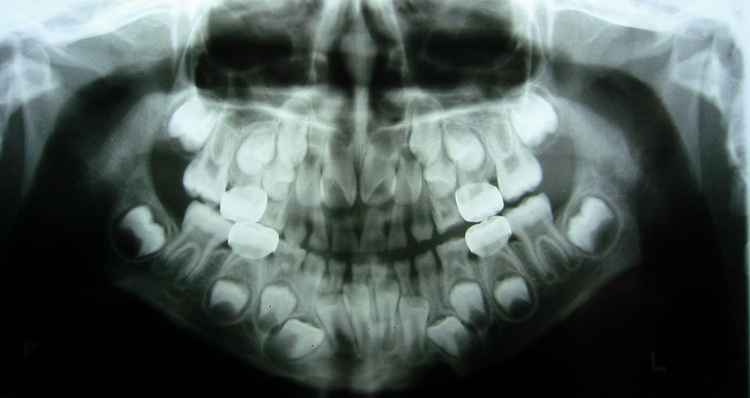

Malocclusion of teeth average cost. If your dog is a big chewer despite this, talk to the veterinarian about recommended toys that are easier on the teeth. Dental xray of a puppy showing how close the developing adult tooth buds are to the roots of the baby teeth. The inside of the tooth fills with infected material that eventually trickles through the openings in the tip of the root into the jaw. Exercise or train your dog every day, tiring him or her out and reducing the urge to chew.

Babies gums are still developing. This side view demonstrates severe tipping. The retained baby tooth is the slender tooth located directly behind the adult canine. Radiographs give us the bigger picture regarding an animal’s dental health by revealing underlying damage that might otherwise be missed. Discussion since an xray is a shadow image of an object through.

The retained baby tooth is the slender tooth located directly behind the adult canine. Radiographs give us the bigger picture regarding an animal’s dental health by revealing underlying damage that might otherwise be missed. This is especially true for smaller breeds with the same number of teeth as dogs with larger mouths but lesser elbow room. Different types of dog teeth. Extraction of the canine was elected!

Note how long and slender the root of the baby canine tooth is. Dogs therefore have two sets of teeth, baby teeth (28), which will eventually fall out, and adult teeth (42). Puppies will start losing their baby teeth when they turn four months old. This is much more difficult to accomplish with a dog than with a human. Malocclusion of teeth average cost.

When our veterinarians clean your dog’s teeth, we check for damaged teeth and “pockets” — much like a dentist does with people. Permanent enamel damage on adult teeth following extraction od deciduous teeth. Babies gums are still developing. You can only see the top third of what’s going on. Note how long and slender the root of the baby canine tooth is.